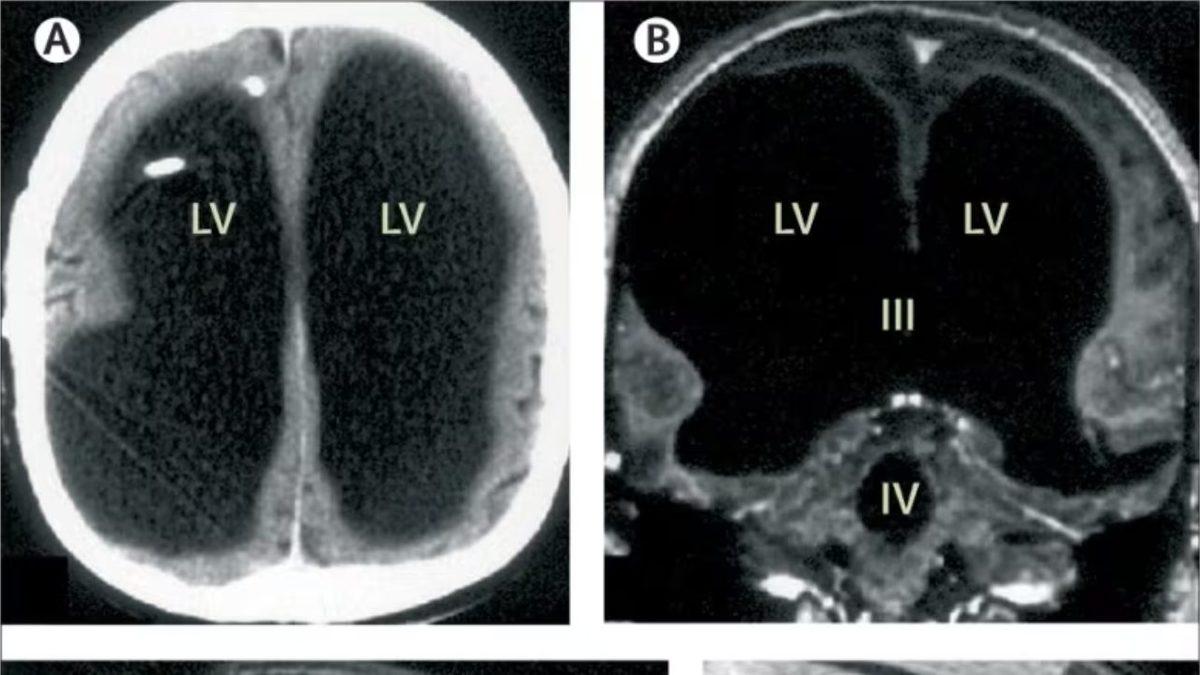

Bu şikayetinin neyden kaynaklandığını bulmaya çalışan doktorlar, yaptıkları beyin taramasında kafatasının büyük kısmının sıvıyla dolu olduğunu gördü. Şaşırtıcı şekilde gerçek beyin dokusunun sadece ince dış tabakası yerindeydi.

Ancak beyninin iç kısmının neredeyse tamamı aşınmış durumdaydı.

Doktorlar ise 44 yaşındaki bu adamın beyninin büyük kısmının, 30 yıl boyunca beyindeki sıvı birikmesiyle yavaş yavaş yok olduğunu düşündü. Bu rahatsızlığın ismi de hidrosefaliydi.